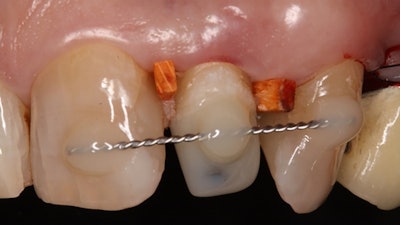

An anchor screw was positioned with the AES.

Prior to the extrusion, patients underwent sufficient endodontic obturation and treatment or retreatment of the fractured tooth. Then, an AES was used to conduct a forced surgical extrusion of a fractured tooth to its required length. It was immediately fixed by two interdental wedges, and, afterward, the anchor screw of the extraction system could be removed, the authors wrote.

All teeth were provided with root canal posts. In some patients, a post was placed adhesively in the same appointment. In others, it was done within 10 weeks after extrusion. The thickest size of the post was selected, which was fitted passively into the prepared core hole of the extrusion apparatus without or with only minimal further drilling.